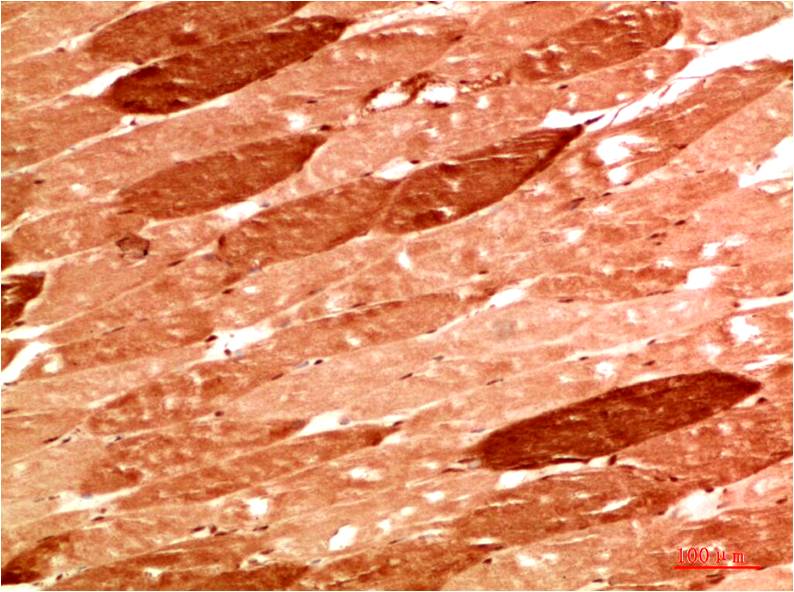

c-Jun Mouse Monoclonal Antibody(4G10)

Applications :IHC

| Recommended dilutions: | IHC 1:100-200 |

| Specificity: | The c-Jun Mouse Monoclonal Antibody can detects endogenous c-Jun proteins. |